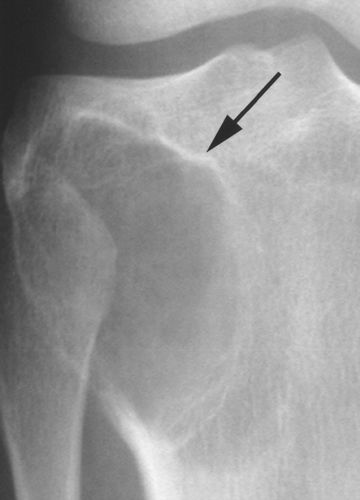

成骨肿瘤很少被误认为骨巨细胞瘤。下面两例为不常见的,成骨细胞瘤(图6)和骨肉瘤(图7)[6,7]。

图6.-38岁女性,成骨细胞瘤。在肱骨近端具有明确的非硬化边缘(箭头)的病灶,与骨巨细胞瘤及其类似。成骨细胞瘤很少有这种外观。